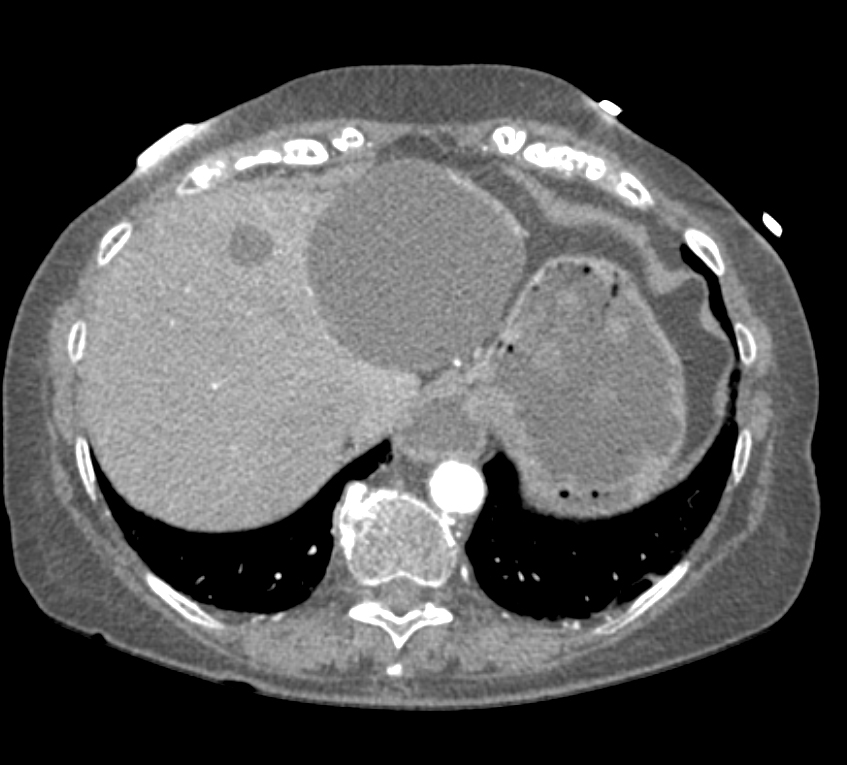

1) The most likely dx in this 50ish yr old male is?

SPEN tumor

serous cystadenoma

pancreatic adenocarcinoma

neuroendocrine tumor (PNET)